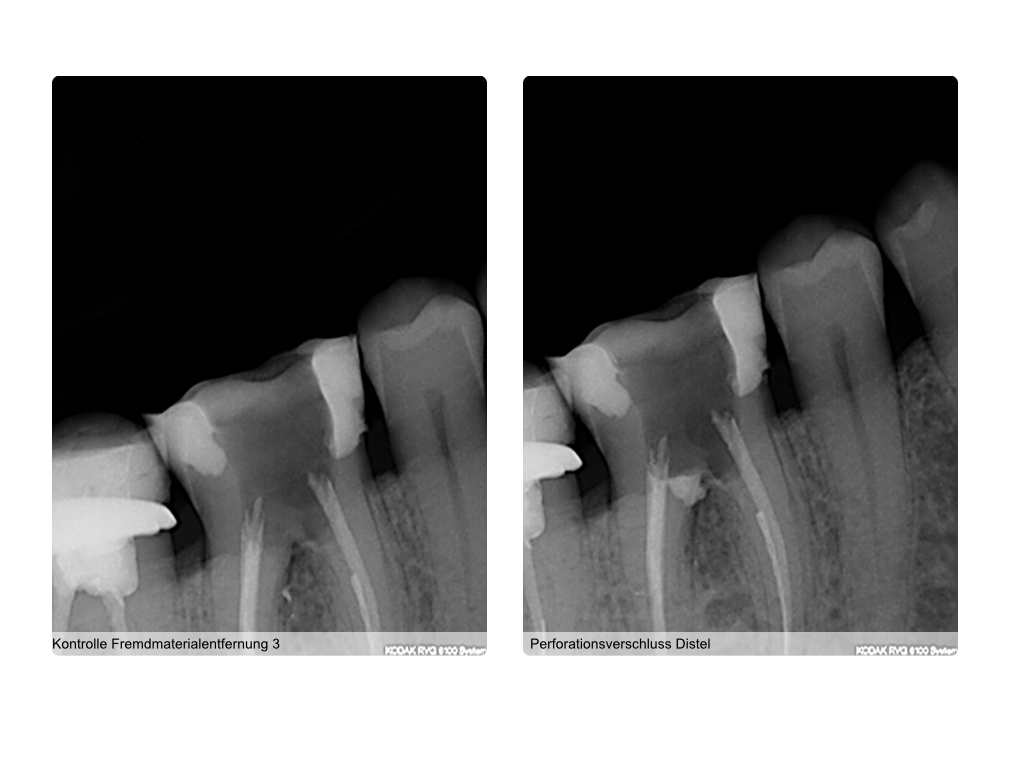

WS 12.008 Veröffentlicht 9. Dezember 2014 am 1024 × 768 in Röntgenauswertung zur Behandlungsplanung (2)